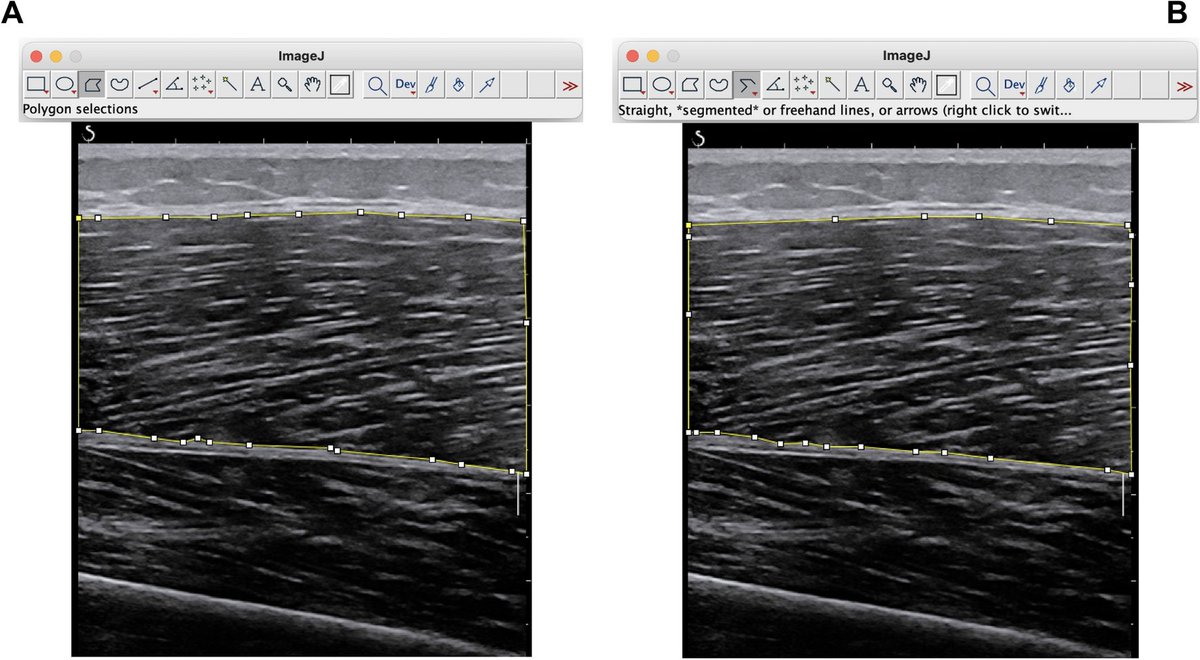

There is a new version of MuscleExpert (1d) with more bug fixes and improvements. zenodo.org/records/180895…

Also, there is a tutorial on YouTube (no audio) with some visuals of how the program works. New tutorials will come soon. youtu.be/Pf1BY5KDT9Q?si…